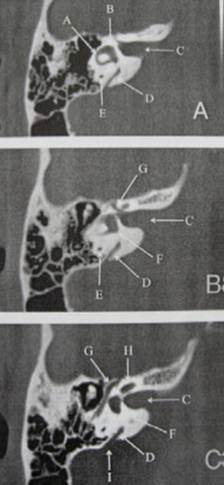

PERTANYAAN 17 – 24

Petunjuk: Jodohkanlah struktur-struktur di bawah ini dengan huruf jawaban yang tepat pada CT scan aksial di bawah ini dari tulang Temporal Petrosus kanan